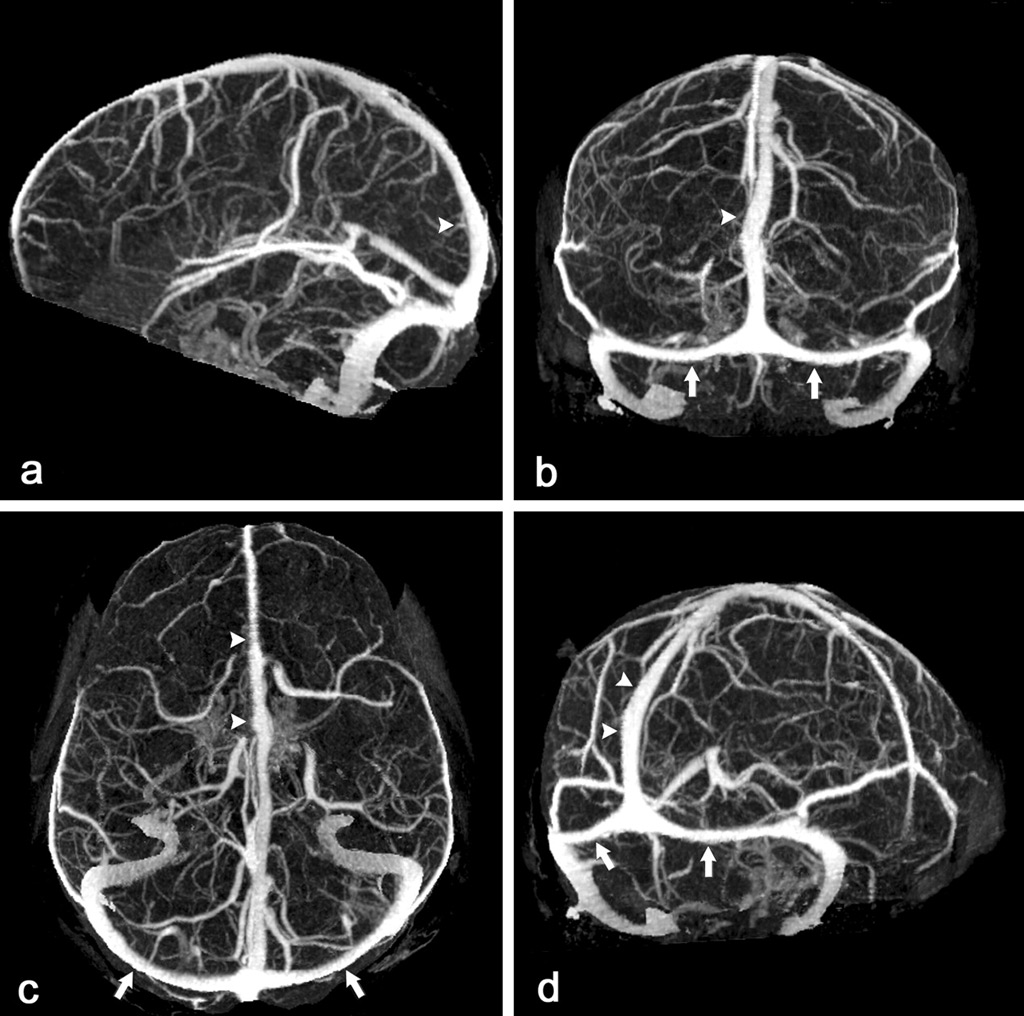

флебографическая визуализация вен и венозных синусов мозга

Флебография (венография) головного мозга выполняется исключительно с помощью установки МРТ или КТ, без введения рентгеноконтрастного препарата. Это связано с тем, что получение серии прицельных снимков, выполняемых послойно, обладает достаточной информативностью и без введения контраста.

Данный вид исследования позволяет подтвердить или исключить патологию венозных синусов, а также поверхностных и глубоких вен головного мозга. Такая патология может быть обусловлена различными заболеваниями (воспалительные – менингоэнцефалит, опухоли, травмы головного мозга, заболевания системы крови), но опасность их заключается в возникновении тромбозов вен указанной локализации. Как правило, при флебографии исследуются венозные синусы головного мозга, вена Галена, внутренние вены головного мозга.

Относительно МРТ-флебографии головного мозга можно сказать, что протокол обследования сложный, со многими нюансами, понятными только специалистам. В случае отсутствия патологических образований в заключении указывается соответствующая фраза; в случае наличия – указываются локализация, размеры и топографическое соотношение патологического образования и здоровых тканей.